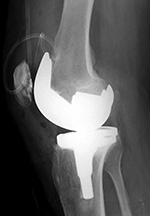

| Biomet XPA Bicruciate Preserving total knee arthroplasty |

Biomet Vanguard 360 Revision Knee System |

| 67 year-old woman. A surgical drain is present from recent surgery. From Taljanovic, 2005 |

This replaced a loose prior total knee arthroplasty. The patellar button was left in place. A surgical drain is in place, and there is subcutaneous gas from the recent surgery. |